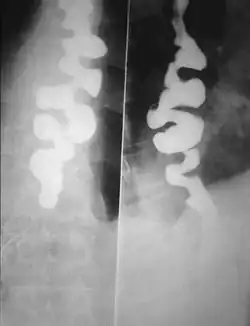

Certain abnormalities on x-ray imaging are commonly observed in DES, such as a "corkscrew esophagus" or "rosary bead esophagus", although these findings are not unique to this condition. Specialized testing called manometry can be performed to evaluate the motor function of the esophagus, which can help identify abnormal patterns of muscle contraction within the esophagus that are suggestive of DES. The treatment of DES consists primarily of medications, such as acid suppressing agents (like proton-pump inhibitors), calcium channel blockers, hyoscine butylbromide, or nitrates. In only extremely rare cases, surgery may be considered. People with DES have higher incidences of gastroesophageal reflux disease (GERD), neuromuscular diseases, and degenerative neurological disorders.

Several radiographic findings are suggestive of DES, such as a "corkscrew esophagus" or "rosary bead esophagus" appearance on barium swallow x-ray, although these findings are not unique to DES.[2]